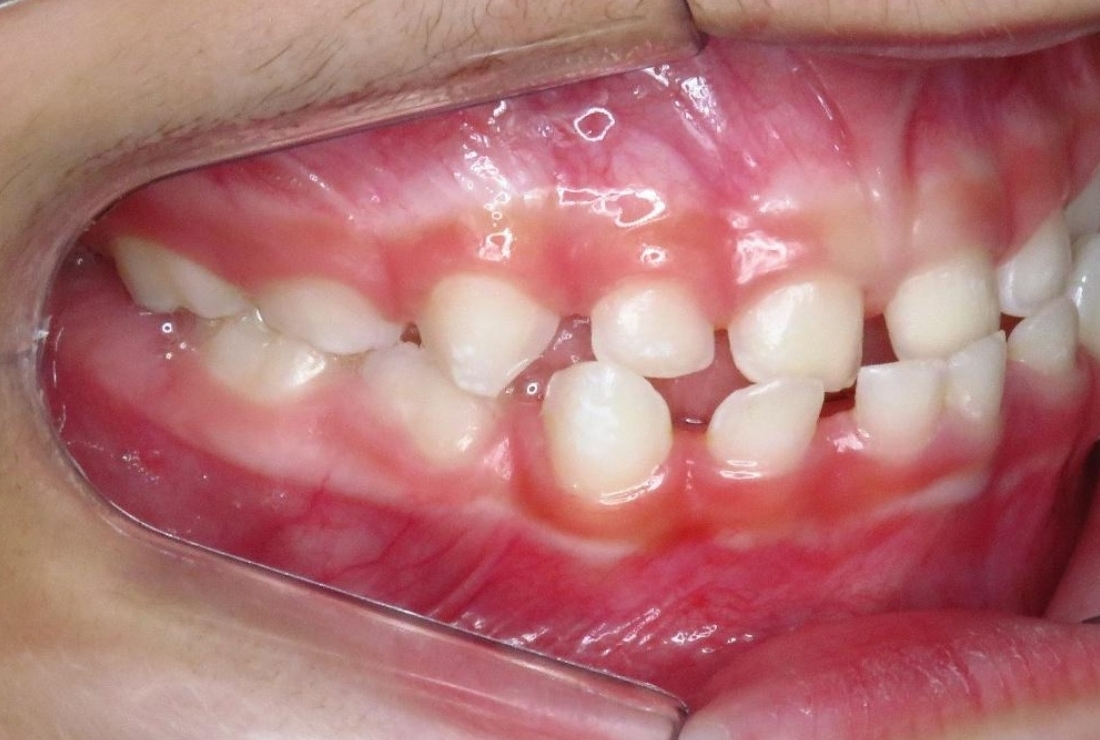

R.P.B.

ORTODONTIA MIOFUNCIONAL